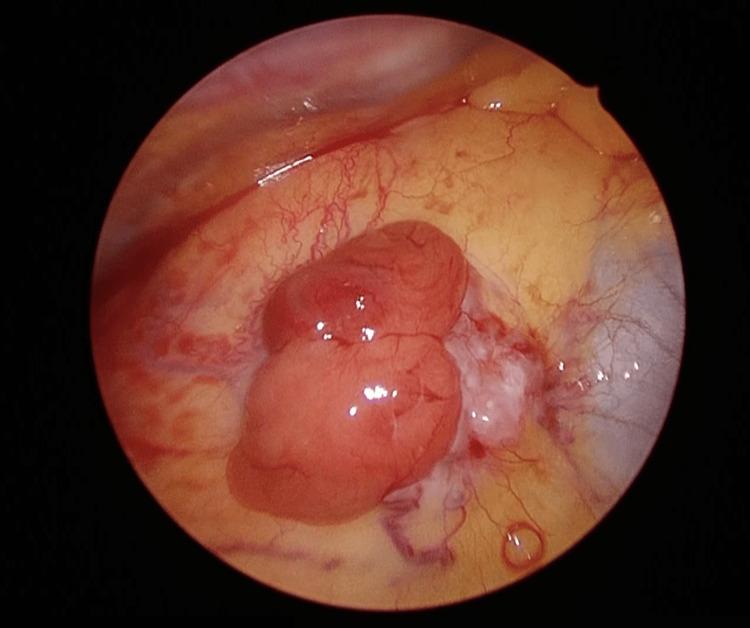

The treatment of multi-organ synchronous neoplasms requires a customized strategy for each case. Here, we present our treatment strategy for synchronous double neoplasms involving thymoma and esophageal cancer, which is a rare occurrence in clinical practice. A 68-year-old man was diagnosed with thymoma and advanced esophageal cancer in the middle thoracic esophagus. Following neoadjuvant chemotherapy for esophageal cancer, a concurrent resection of both lesions was performed using minimally invasive unilateral video-assisted thoracoscopic surgery and laparoscopic surgery with gastric conduit reconstruction via the posterior mediastinal route. The patient was discharged on the 14th postoperative day without any adverse events. Minimally invasive, video-assisted unilateral simultaneous surgery for thymoma and esophageal cancer represents a viable therapeutic approach, offering both curative potential and decreased invasiveness. Furthermore, reconstructing the gastric conduit via the posterior mediastinal route was deemed appropriate, as it may help minimize the risk of invasion of the gastric conduit and radiation exposure in the event of thymoma disease progression. Additionally, we propose a treatment strategy flow for synchronous neoplasms located in adjacent multi-organs. This strategy can be applied to various tumor types and may benefit other complex cases.

多器官同步性肿瘤的治疗需要针对每个病例制定个性化策略。在此,我们展示了针对同时发生的胸腺瘤和食管癌这一临床实践中罕见情况的治疗策略。一名68岁男性被诊断患有胸腺瘤和胸段食管中段的晚期食管癌。在对食管癌进行新辅助化疗后,采用微创单侧电视辅助胸腔镜手术和腹腔镜手术经后纵隔途径重建胃管道,同时切除两个病灶。患者术后第14天出院,无任何不良事件。微创、电视辅助单侧同步手术治疗胸腺瘤和食管癌是一种可行的治疗方法,具有治愈潜力且侵袭性降低。此外,经后纵隔途径重建胃管道被认为是合适的,因为在胸腺瘤疾病进展时,这可能有助于将胃管道受侵犯的风险和辐射暴露降至最低。此外,我们提出了一种针对位于相邻多器官的同步性肿瘤的治疗策略流程。该策略可应用于各种肿瘤类型,可能使其他复杂病例受益。